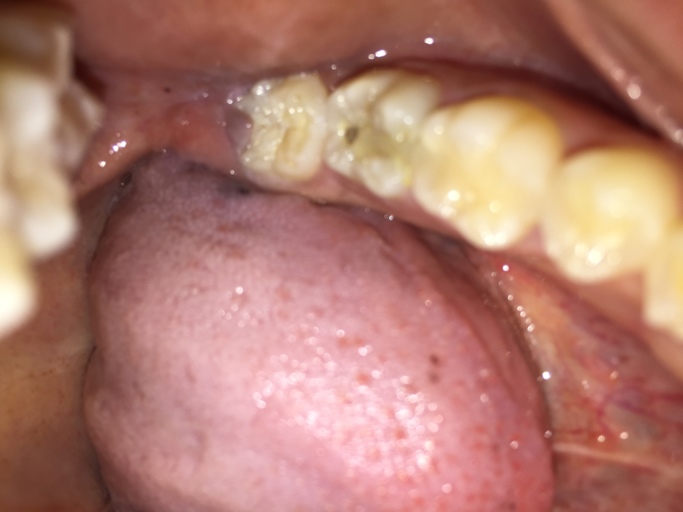

How to know if need a root canal?

I have swelling in my cheek. I have pain in my tooth and under my gum I have a large bump which I causing the swelling I think and it hurts and I want to know what it is and if I need a root canal? In the photo it is the molar with filling that you can see the most

I have swelling in my cheek. I have pain in my tooth and under my gum I have a large bump which I causing the swelling I think and it hurts and I want to know what it is and if I need a root canal? In the photo it is the molar with filling that you...